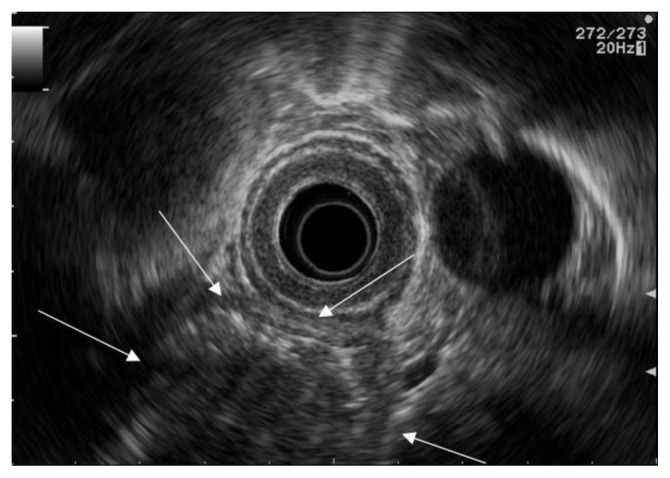

Figure 2.

62 year old male with carcinoma in esophageal diverticulum. Endoscopic ultrasound with 5 MHz radial echoendoscope (GF-UM140, Olympus America Inc., Melville, NY) advanced in to the esophagus, to the level of diverticulum, showing hypoechoic mass (arrows) measuring 3.6 × 3.1 × 3.4 cm in the esophageal diverticulum.